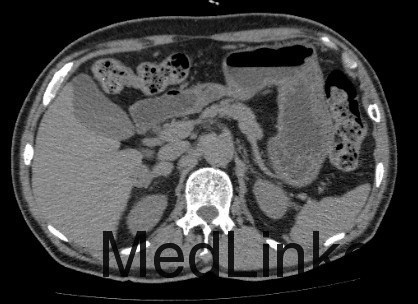

查体: 左上腹外侧见手术切除,余无异常。 辅助检查: 1、检验 白细胞WBC 6.15x10^9/L,血红蛋白Hb 165 g/L,血小板PLT 173x10^9/L;乙肝表面抗原HBsAg(-),乙肝核心抗体HBcAb(+);AFP, CEA、CA125、CA19-9均正常范围 2、影像学 CT:肝S6内缘包膜下结节(19×17mm、19×19mm,),考虑肝细胞癌可能性大,建议进一步检查;其相邻低密度结节,不除外肝囊肿。 2.右侧肾上腺结节,考虑转移瘤可能性大。 3.双肾囊肿。

临床诊断 肝细胞癌 治疗: 手术切除右侧肾上腺转移瘤和右肝肿瘤 术后病理: 1、(肝)送检4x3x2cm灰褐色组织一块,切面灰黄,质软。 镜下:送检肝组织内见境界较清楚的胶原纤维包裹的坏死结节,其内可见肿瘤残影,建议结合临床患者是否行介入等治疗,则可符合治疗后改变,未见残留肿瘤细胞。另一组织提示增生的肝细胞Glypican-3灶性(+),CD34显示增生的结节毛细血管化。 特殊染色:网状纤维染色显示肝细胞索增生。 结合HE形态及免疫组化结果,病变符合肝细胞癌。 2(肾上腺结节)送检5x3x3cm淡黄组织一块,可见直径2cm灰白结节。 镜下:肾上腺组织内见肝细胞癌浸润。